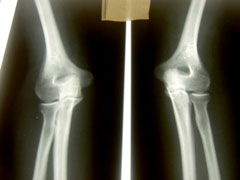

肘の痛みは大きく分けて外側の外側上顆炎と内側上顆炎があります。

外側→テニス肘

内側→野球肘

というような感じで呼ばれています。

・上腕骨外側上顆炎は主に腕の伸筋群(手首、指を伸ばす筋肉)に負担がかかり伸筋腱や骨膜が炎症を起こし痛みを出します。稀に筋断裂を起こし、内出血を見られることがあります。

手作業を強いられる職種の方、肘や手首を酷使する主婦に多く認められます。また、バックハンドを多用するテニスプレイヤーに多いため、別名「テニス肘」とも呼ばれています。

症状は運動時や作業時の肘の外側の痛みです。特に、肘を伸ばした状態で物を持つ時に痛みを訴えます。

・上腕骨内側上顆炎は主に腕の屈筋群(手首、指を曲げる筋肉)に負担がかかり屈筋腱や骨膜が炎症を起こし痛みを出します。外側上顆炎と似ていますね。

ボールを投げるときに屈筋に力が入るため、別名「野球肘」とも呼ばれています。

症状は肘の内側に痛みが出ることです。